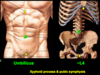

Umbilicus

- What is it?

- Where is it located (on a person with low body fat)?

Umbilicus

- Former site of attachment of umbilical cord

- Location varies with age and body contours

- In a person with low body fat, the umbilicus lies at L4 vertebral level and is midway between the xiphoid process and public symphysis

What are the abdominal planes and where do they pass through? What do two these planes form?

Transumbilical plane - passes horizontally through the umbilicus at L4 vertebral level (corresponding to level of the iliac crests)

Median plane - pass vertically through the body midline, from the xiphoid process to the pubic sympysis